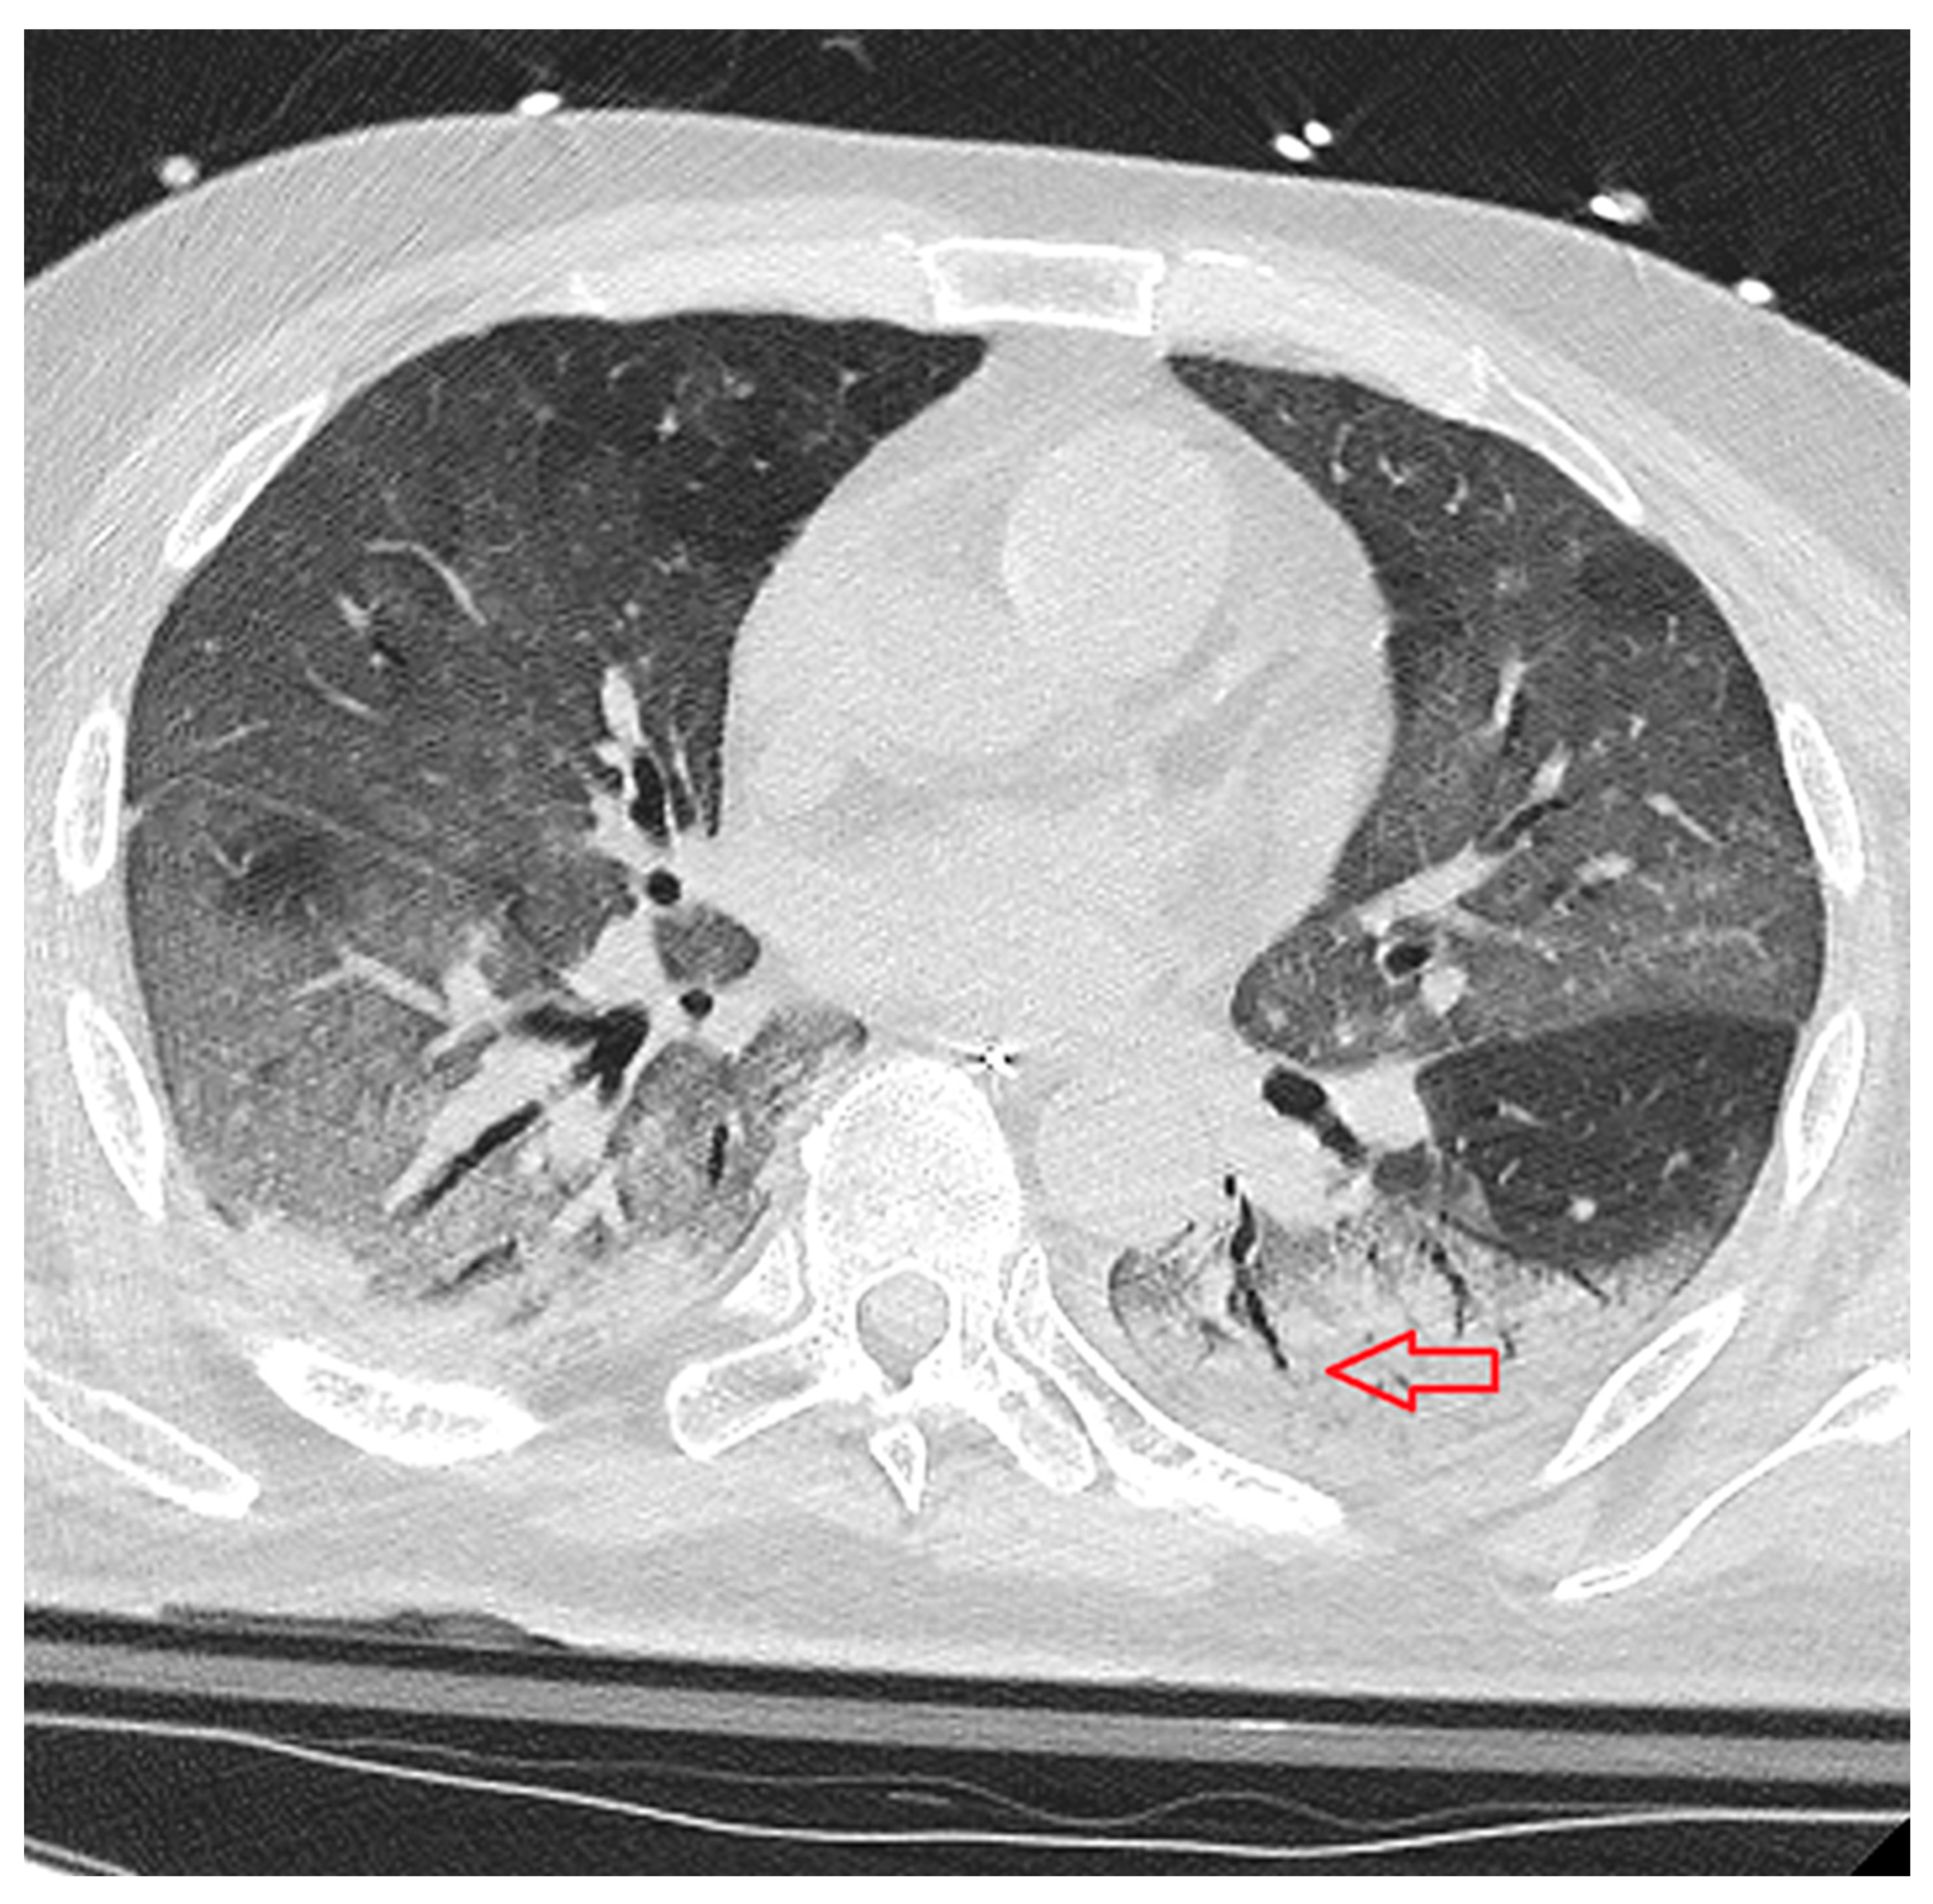

- Subpleural curvilinear line: thin, curved opacity 1–3 mm thick, less than 1 cm from and parallel to the pleural surface (Figure 4);